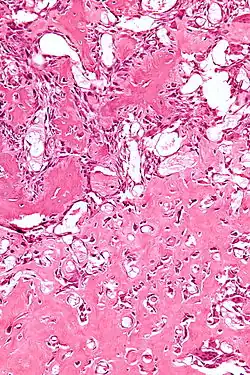

Micrograph of an osteoblastoma H&E stain

The cause of osteoblastoma is unknown. Histologically, osteoblastoma are similar to osteoid osteomas, producing both osteoid and primitive woven bone amidst fibrovascular connective tissue, the difference being that osteoblastoma can grow larger than 2.0 cm in diameter while osteoid osteomas cannot. Although the tumor is usually considered benign, a controversial aggressive variant has been described in the literature, with histologic features similar to those of malignant tumors such as an osteosarcoma.[4]